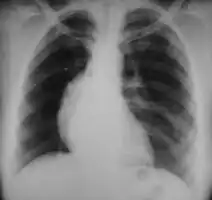

- Lymphadenopathy: the most common symptom of Hodgkin is the painless enlargement of one or more lymph nodes.[14] The nodes may also feel rubbery and swollen when examined. The nodes of the neck and shoulders (cervical and supraclavicular) are most frequently involved (80–90% of the time, on average).[14] The lymph nodes of the chest are often affected, and these may be noticed on a chest radiograph.[14]

After Hodgkin lymphoma is diagnosed, a person will be staged: that is, they will undergo a series of tests and procedures that will determine what areas of the body are affected. These procedures may include documentation of their histology, a physical examination, blood tests, chest X-ray radiographs, computed tomography (CT)/Positron emission tomography (PET)/magnetic resonance imaging (MRI) scans of the chest, abdomen and pelvis, and usually a bone marrow biopsy. Positron emission tomography (PET) scan is now used instead of the gallium scan for staging. On the PET scan, sites involved with lymphoma light up very brightly enabling accurate and reproducible imaging.[29] In the past, a lymphangiogram or surgical laparotomy (which involves opening the abdominal cavity and visually inspecting for tumors) were performed. Lymphangiograms or laparotomies are very rarely performed, having been supplanted by improvements in imaging with the CT scan and PET scan.